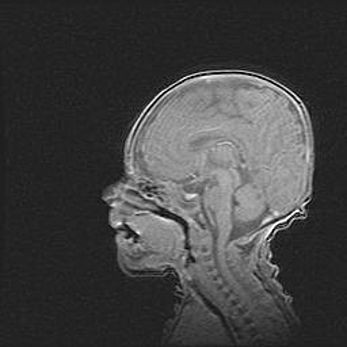

Церебральная ишемия II.

Возраст: 5 дней

Вес: 3400 г

Пол: женский

Окружность головы: 35 см

Срок гестации: 39 недель

Церебральная ишемия – это заболевание, характеризующееся недостаточностью (гипоксией) либо полным прекращением (аноксией) снабжения мозга кислородом по причине закупорки одного или нескольких сосудов. Это приводит к  что метаболическим расстройствам различной степени тяжести в тканях головного мозга, развитию коагуляционных некрозов и гибели нейронов.